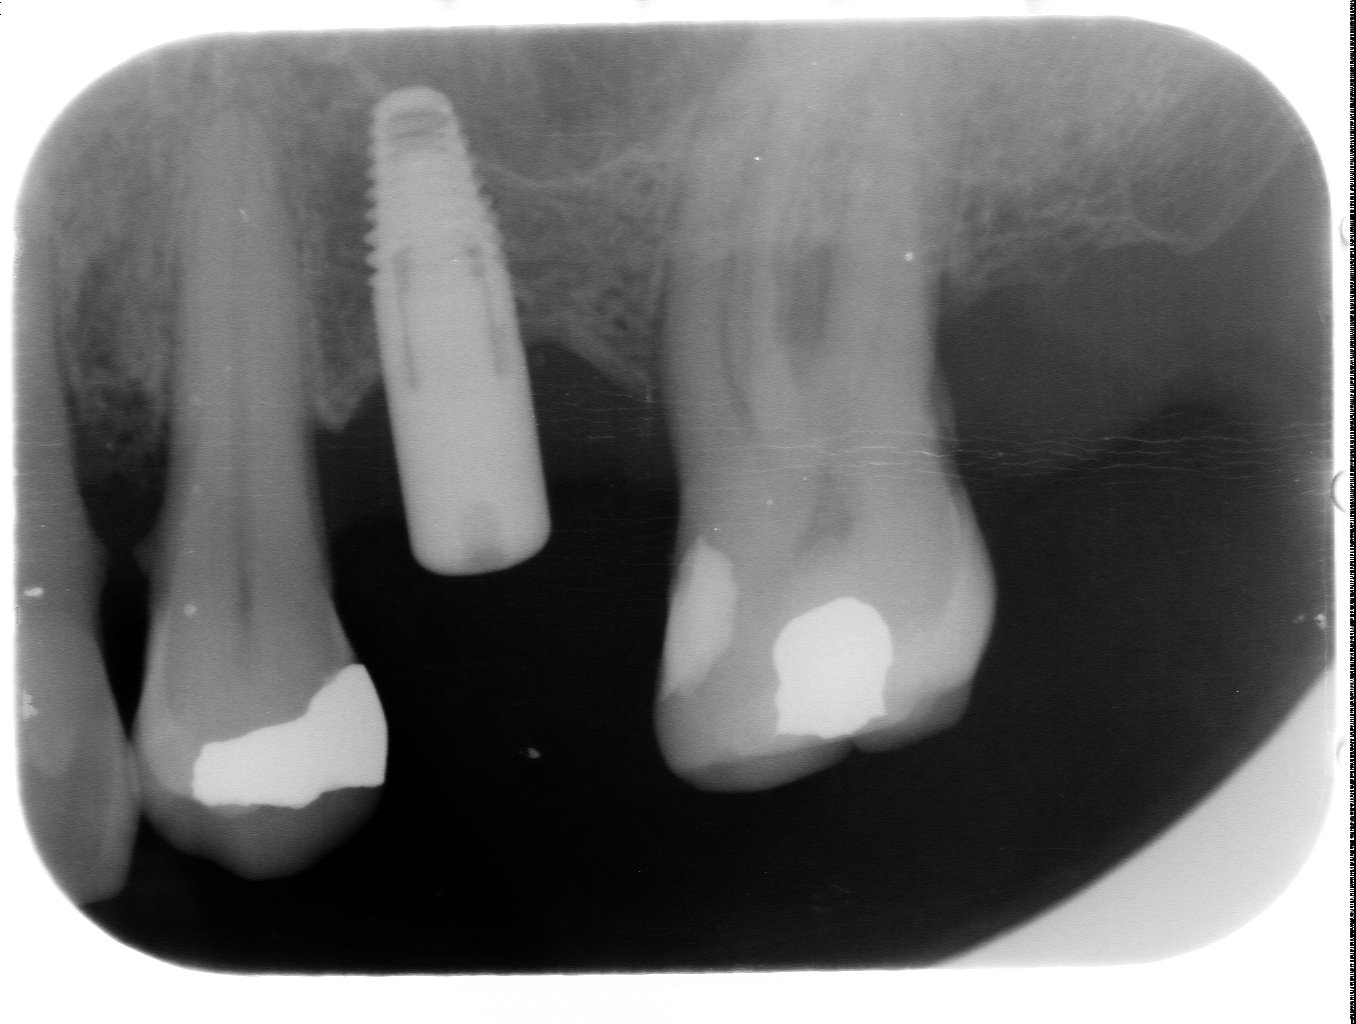

Muy buenas compañeros, necesito ayuda para averiguar que implante es en la posición 33. El ioi se colocó en iDENTAL y está integrado. Presenta una conexión hexagonal externa. El paciente [...]